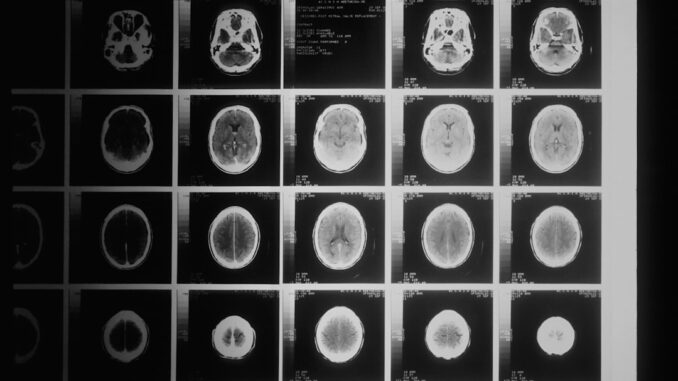

What happens next is crucial: this mechanical stress temporarily, and reversibly, loosens the ‘tight junctions’ between these endothelial cells. Imagine the bricks of a wall briefly separating just enough to create microscopic gaps. These fleeting openings, just nanometers wide, are precisely what we need. They allow therapeutic agents, like chemotherapy drugs, which are normally too large or hydrophilic to cross the intact BBB, to slip through these temporary fissures and directly access the tumour site. It’s a remarkably controlled process, one that can be precisely monitored in real-time using advanced imaging techniques, ensuring that only the target area is affected, and surrounding healthy brain tissue remains largely undisturbed. The beauty of it, it’s reversible too; once the FUS treatment stops, the BBB re-establishes its integrity within a matter of hours. Quite clever, wouldn’t you say?

Think about the courage these families showed, consenting to a completely novel procedure for their children, knowing the stakes were incredibly high. The methodology was meticulous: patients with progressive DMG, for whom standard treatments had already failed, were carefully selected. The FUS procedure, guided by MRI for exquisite precision, targeted the tumour site in the brainstem. Following the FUS-induced BBB opening, a standard chemotherapy drug, often irinotecan, was administered intravenously, hoping it could now finally reach its intended target.